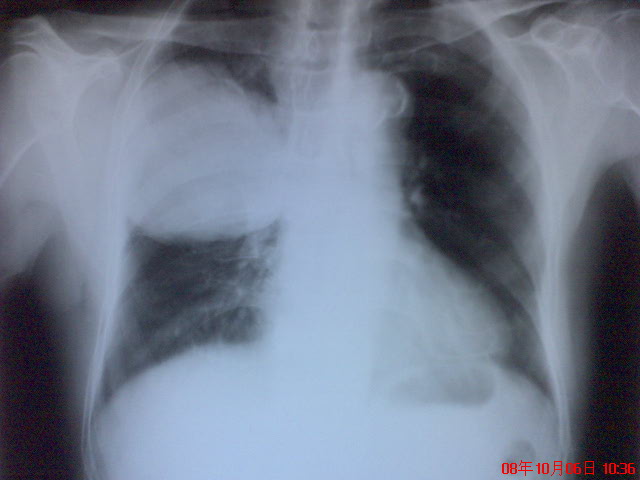

患者作过ct检查,结论是右中上肺占位,考虑直肠癌肺转移?,肺横纹肌肉瘤?,血管平滑肌瘤?建议进一步检查.因家境贫寒,没能做病检。

右中上肺占位,考虑直肠癌肺转移?,肺肉瘤?

只能考虑右上肺巨大占位,至于是结肠癌转移还是肺癌肉瘤没有特征性改变,应结合病理检查。

右上肺占位,考虑1周围型肺癌,2肺肉瘤

考虑右中上肺巨大占位。结肠癌转移还是肺癌肉瘤,结合病理再诊断吧